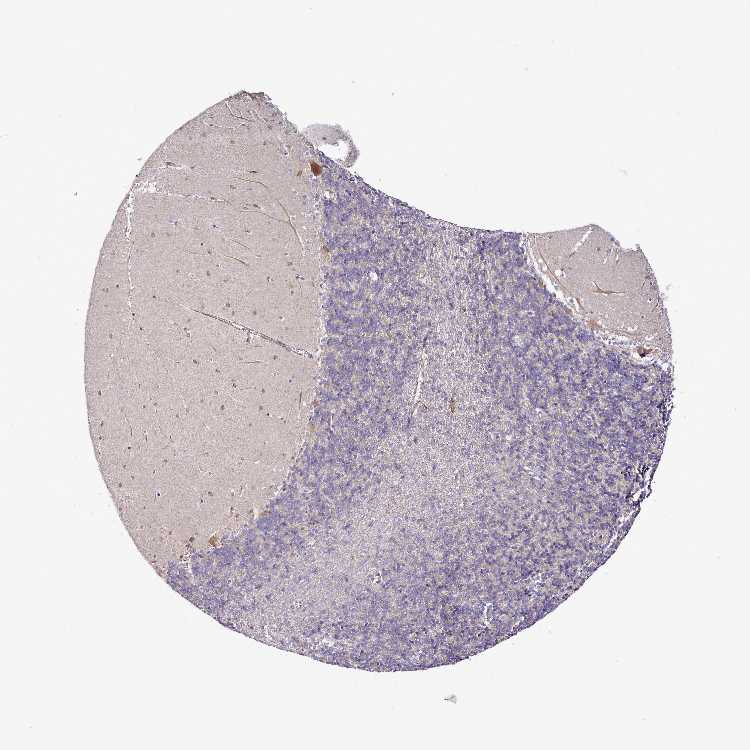

BRAIN CEREBELLUM Show tissue menu

CEREBELLUM - Expression summary

Protein expression

Cerebellumi

On the top, protein expression in current human tissue, based on all annotated cell types, is reported with the units not detected (n), low (l), medium (m) and high (h). Underneath, protein expression in each annotated cell type are reported using the same units.

Protein expression data is based on knowledge-based annotation. For genes where more than one antibody has been used, a collective score is set.

If knowledge-based annotation could not be performed for a gene, no data is displayed here. View antibody staining data further down this page.

Cells in granular layer: Low

Cells in molecular layer: Low

Purkinje cells: Medium

CEREBELLUM - Antibody stainingi

Antibody staining in the annotated cell types in the current human tissue is reported as not detected, low, medium, or high, based on conventional immunohistochemistry profiling in selected tissues. This score is based on the combination of the staining intensity and fraction of stained cells.

Each image is clickable and will lead to virtual microscopy that enables deeper exploration of all samples and also displays staining intensity scores, fraction scores and subcellular localization as well as patient and tissue information for each sample.

Antibody HPA038748Antibody HPA042595Antibody HPA043105Antibody HPA043692Antibody HPA044023Antibody HPA046971Antibody HPA058050

Purkinje cells MediumNot detectedHighNot detectedNot detectedNot detectedNot detected

Cells in granular layer LowNot detectedNot detectedNot detectedNot detectedNot detectedNot detected

Cells in molecular layer LowNot detectedNot detectedNot detectedNot detectedNot detectedNot detected